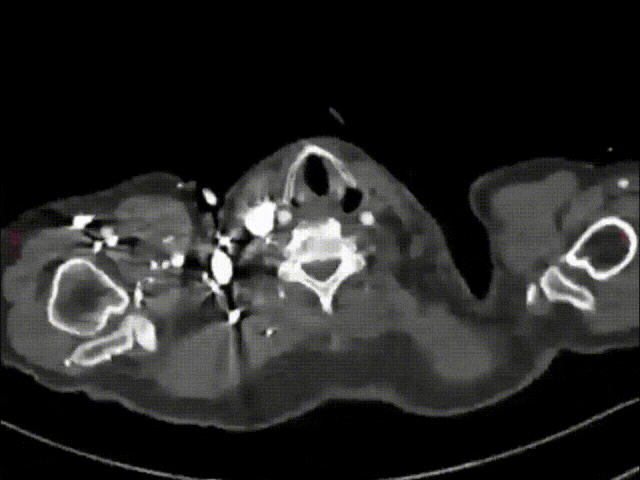

★ Case 4

男性,71岁,间断胸痛半年,加重7+天

高血压1+年,收缩压最高160+ mmHg

既往史和手术史:保守治疗1+月,弓部血肿增厚,胸痛加重

夹层动脉瘤CTA:主动脉夹层(非A非B型),累及主动脉弓至腹腔干发出平面以上腹主动脉,真腔小,假腔大;主动脉弓及左颈总动脉、左锁骨下动脉近端管径增粗,合并壁内血肿

术前影像